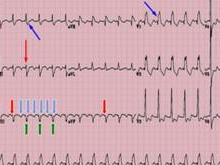

心房内传导阻滞(intra-atrial block)简称房内阻滞,是指自窦房结发出的冲动在心房内传导时间延长或中断,分为不完全性和完全性传导阻滞。正常窦房结发出激动是沿结间束传至房室结,同时沿房间束(Bachmann 束)从右心房传到左心房。患者可有胸闷、气促、心跳不齐等症状。